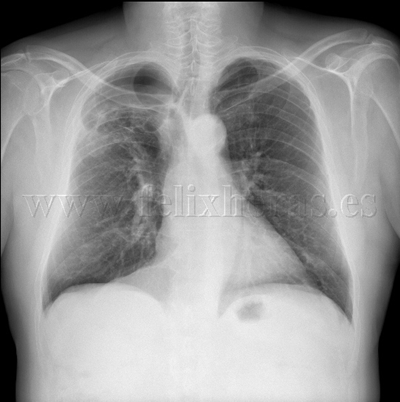

Enfisema pulmonar